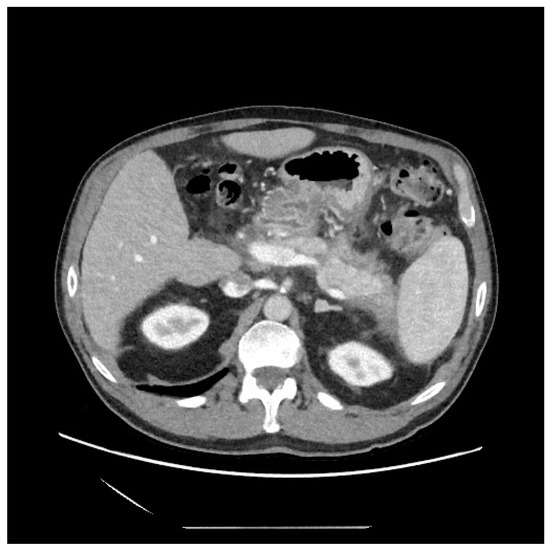

2. Case Presentation